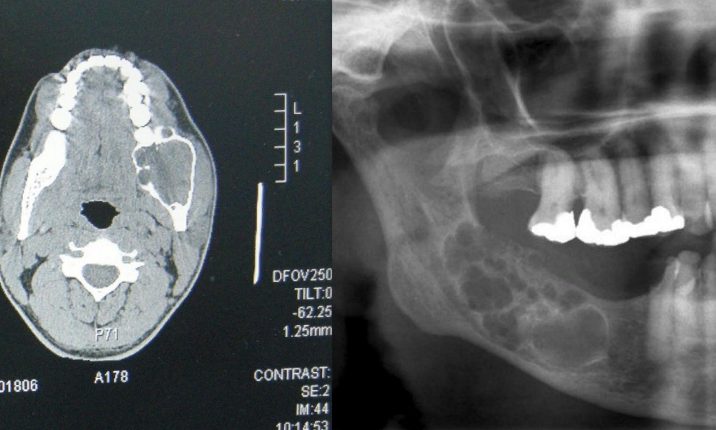

Фото Рак Нижней

Фото Рак Нижней 115 фото